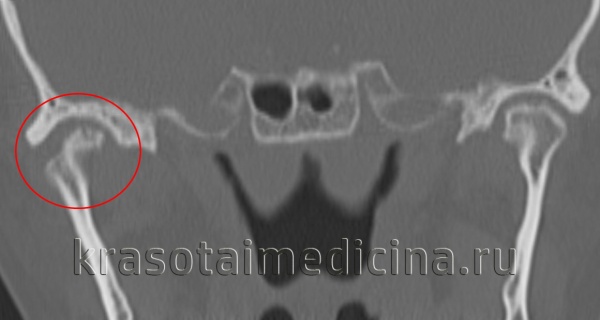

(Слева) На корональной КТ без КУ у этого же пациента определяется выраженное увеличение правого мыщелка, соединенного с височной костью костным мостиком с наружной стороны. Суставное пространство облитерировано. Шейка мыщелка и ветвь нижней челюсти утолщены.